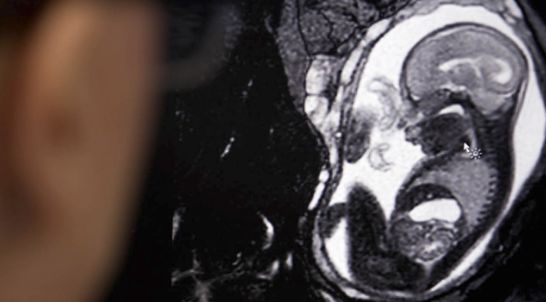

MRI掃描顯示胎兒脊椎彎曲

此前,他們與家人一起前往得克薩斯州,懷孕24周的Kimmie在那里做了一次常規(guī)的產(chǎn)檢,意外得知自己未出生的兒子患有脊柱裂,而且胎兒脊柱的彎曲程度相當嚴重(這種情況被稱為脊柱后凸)。這個消息讓McCaw夫婦倆心碎,因為他們的孩子很可能患有持續(xù)性的Chiari畸形,這是某種脊柱裂的典型并發(fā)癥,會導致脊髓液過度積聚,如不及時治療,就會有腦損傷、癲癇或失明的風險。